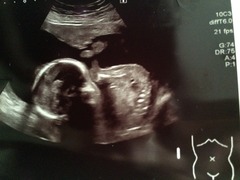

I've had a whirlwind of a day. Spent most of the morning in floods of tears as I fell over on my way to 20 week scan. There was something wet on the living room floor which I skidded on. Thank god I fell on my back rather than bump but it gave me a terrible fright and I was convinced I'd get bad news at hospital. Have attached 2 pics - second is very cute one of baby putting legs on head.

Luckily scan went really well and everything was absolutely fine. He refused to face the camera so I had a little walk and can of lemonade that got him moving! Will

Great pics Carla especially the legs on head one!! Congratulations on completing on the flat too. Sorry your not feeling great about it all. Maybe it's hormones playing a part. I'm sure it'll feel different once your in and it feels properly yours. Does it need work/decorating? X

Carla great scan pics. Glad all went well.

Carla congratulations on the flat and the scan. I always think big moments like that are never how I imagined they would be! Just think about how lovely it will be to be in the flat with your little baby in the summer Smile

Carla - lovely scan pics and congrats on house purchase. I totally know what you mean about no one sharing the good news tho and empty places are, well, empty. But a bit of ikea and eBay will do wonders as will a new day. my advice : house plants and tea lights all the way!

Carla lovely pic, congrats.